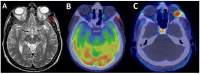

Solitary fibrous tumor (SFT) of the central nervous system, previously named and classified with the term hemangiopericytoma (HPC), is rare and accounts for less than 1% of all intracranial tumors. Despite its benign nature, it has a malignant behavior due to the high rate of recurrence and distant metastasis, occurring in up to 50% of cases. Surgical resection of the tumor is the treatment of choice. Radiotherapy represents the gold standard in the case of post-surgery residual disease, relapse, and distant metastases. In this context, imaging plays a crucial role in identifying the personalized therapeutic decision for each patient. Although the referring imaging approach in SFT is morphologic, an emerging role of positron emission tomography (PET) has been reported in the literature. However, there is still a debate on which radiotracers have the best accuracy for studying these uncommon tumors because of the histological or biological heterogeneity of SFT.